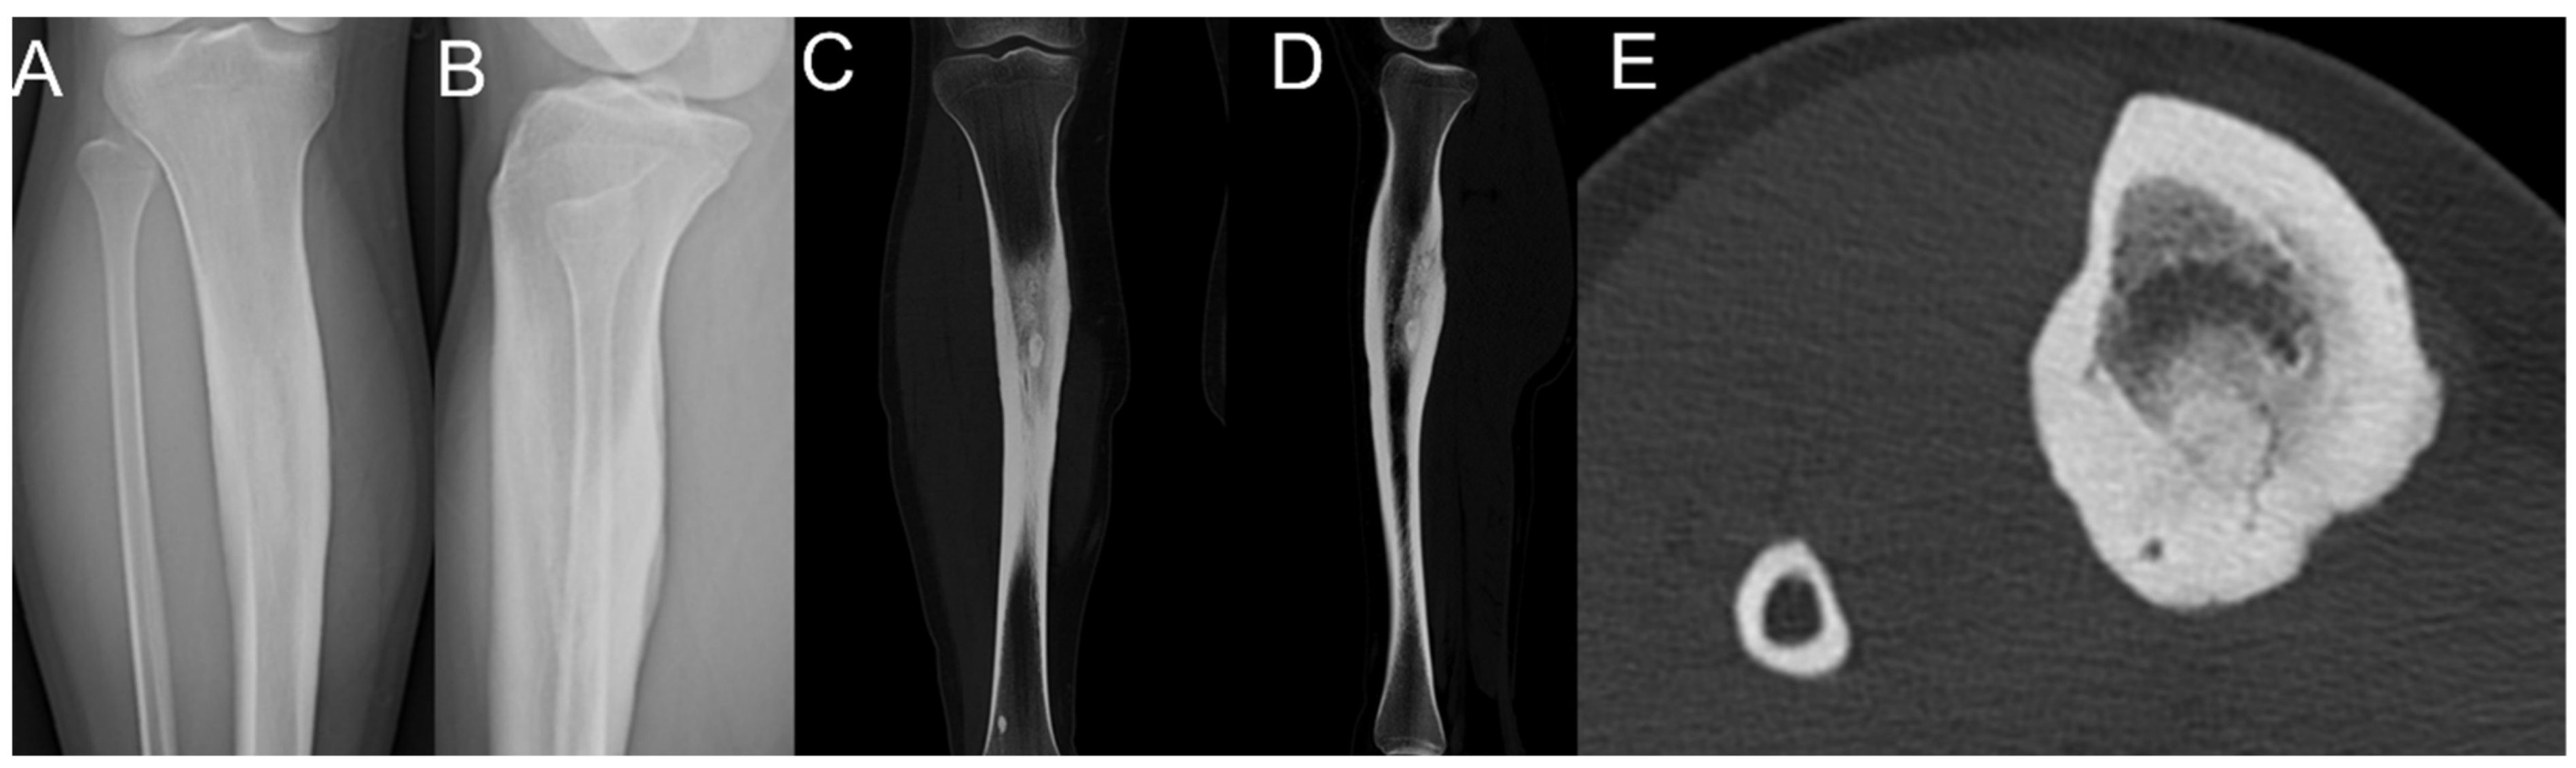

2.1. Case 1